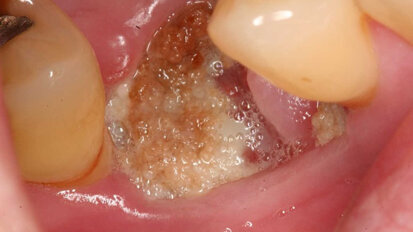

Study presents new treatment for jaw osteonecrosis around dental implants

SEOUL, South Korea: Dental implants are a key treatment for tooth loss, but can cause a variety of complications. One such complication is osteonecrosis, ...